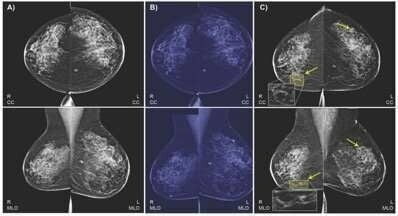

- Результаты визуализации, данные о здоровье объединяются в модели ИИ для прогнозирования рака молочной железы.